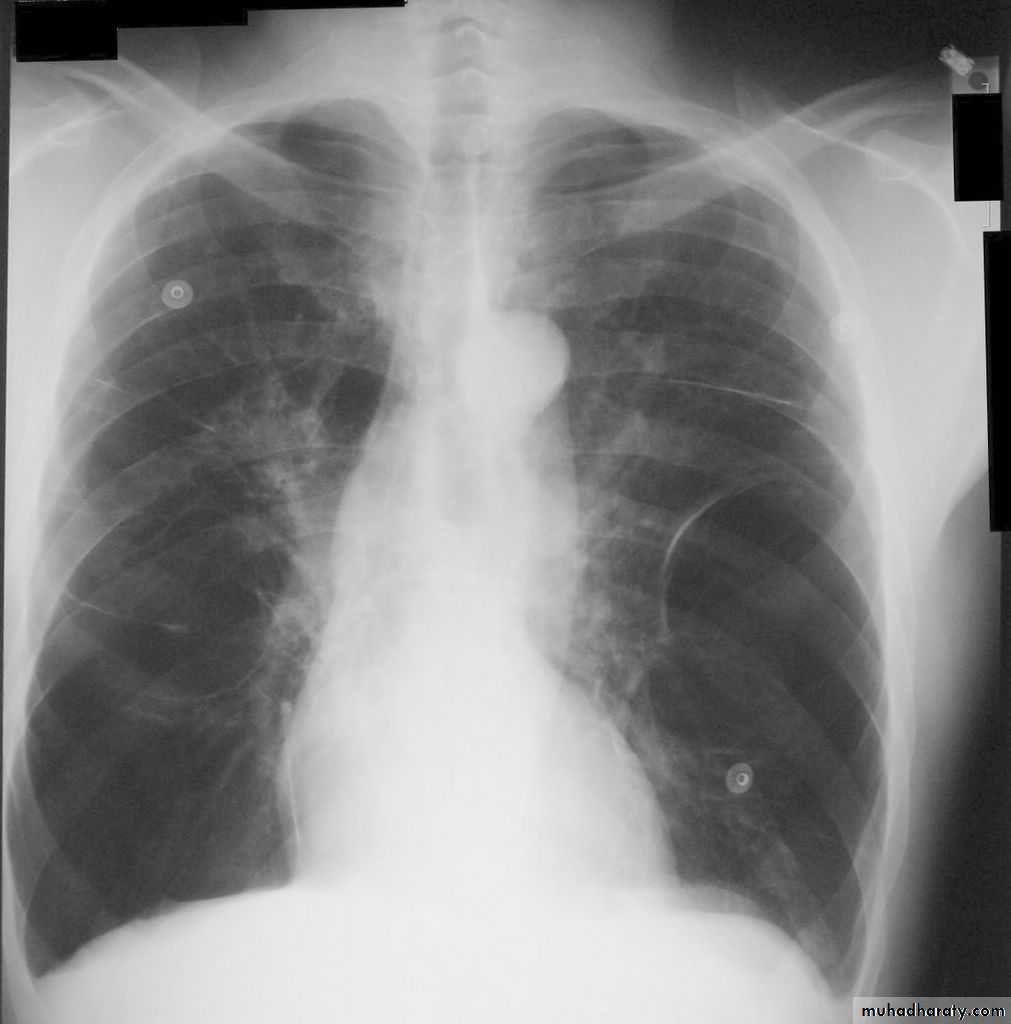

Investigations Imaging

Chest X-ray: typical changes of emphysema include paucity of parenchymal markings, hyper-translucency and bulae. Increasing lung volume and flattening of diaphragm suggest hyperinflation.